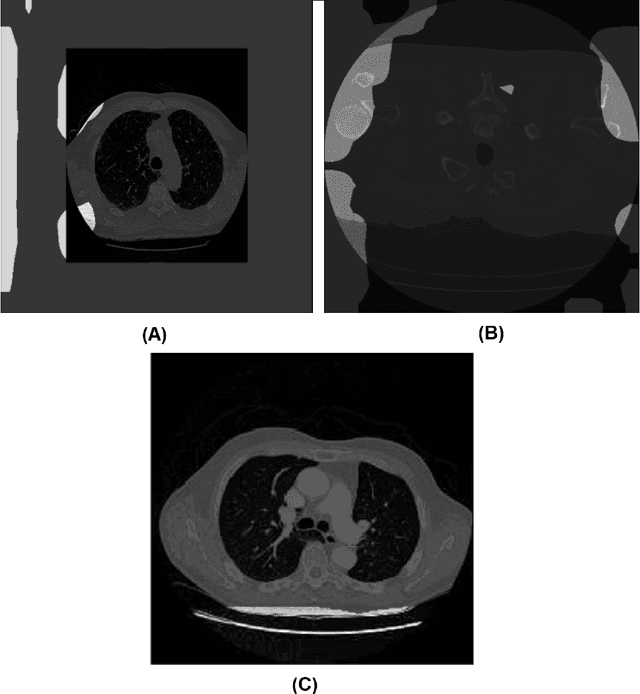

Abstract:In this study, we take a departure and explore an explainability-driven strategy to data auditing, where actionable insights into the data at hand are discovered through the eyes of quantitative explainability on the behaviour of a dummy model prototype when exposed to data. We demonstrate this strategy by auditing two popular medical benchmark datasets, and discover hidden data quality issues that lead deep learning models to make predictions for the wrong reasons. The actionable insights gained from this explainability driven data auditing strategy is then leveraged to address the discovered issues to enable the creation of high-performing deep learning models with appropriate prediction behaviour. The hope is that such an explainability-driven strategy can be complimentary to data-driven strategies to facilitate for more responsible development of machine learning algorithms for computer vision applications.

Abstract:Pulmonary fibrosis is a devastating chronic lung disease that causes irreparable lung tissue scarring and damage, resulting in progressive loss in lung capacity and has no known cure. A critical step in the treatment and management of pulmonary fibrosis is the assessment of lung function decline, with computed tomography (CT) imaging being a particularly effective method for determining the extent of lung damage caused by pulmonary fibrosis. Motivated by this, we introduce Fibrosis-Net, a deep convolutional neural network design tailored for the prediction of pulmonary fibrosis progression from chest CT images. More specifically, machine-driven design exploration was leveraged to determine a strong architectural design for CT lung analysis, upon which we build a customized network design tailored for predicting forced vital capacity (FVC) based on a patient's CT scan, initial spirometry measurement, and clinical metadata. Finally, we leverage an explainability-driven performance validation strategy to study the decision-making behaviour of Fibrosis-Net as to verify that predictions are based on relevant visual indicators in CT images. Experiments using the OSIC Pulmonary Fibrosis Progression Challenge benchmark dataset showed that the proposed Fibrosis-Net is able to achieve a significantly higher modified Laplace Log Likelihood score than the winning solutions on the challenge leaderboard. Furthermore, explainability-driven performance validation demonstrated that the proposed Fibrosis-Net exhibits correct decision-making behaviour by leveraging clinically-relevant visual indicators in CT images when making predictions on pulmonary fibrosis progress. While Fibrosis-Net is not yet a production-ready clinical assessment solution, we hope that releasing the model in open source manner will encourage researchers, clinicians, and citizen data scientists alike to leverage and build upon it.